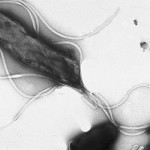

Los investigadores construyeron una vacuna bacteriana viva recombinante, que expresa el antígeno H. pylori, adhesina Hp0410, en la bacteria de calidad alimentaria, Lactobacillus acidophilus. Luego utilizaron para vacunar a los ratones por vía oral.

H. pylori es un carcinógeno de clase 1, según la Organización Mundial de la Salud. Provoca gastritis, úlceras pépticas, cáncer de estómago, y linfoma del tejido linfoide asociado a la mucosa. El tratamiento antibiótico es complejo, sin éxito en algunos pacientes (especialmente en los países en desarrollo) y la recaída es común. Una vacuna contra H. pylori podría eludir estas dificultades.